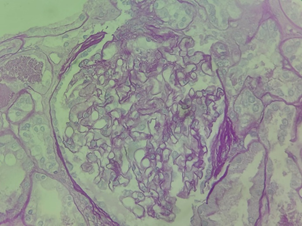

A skin biopsy was performed with IgM and C3 deposits associated with thrombocytopenia, bilirubin elevation, and acute renal failure, and the condition was compatible with aHUS Figure 1–5. Treatment with Intravenous Immune Globulin (IVIG) and Dexamethasone was started from 08/24 to 08/29/2023 and Eculizumab was started on 08/25/2023. A patient with prolonged hospitalization for three months, diagnosed with rare diseases, developed pulmonary thromboembolism, deep vein thrombosis of the right lower limb, and was anticoagulated with Apixaban. He was discharged and one month after discharge, he recovered his kidney function, using Ecolizumab, no longer requiring hemodialysis, in addition to the exchange of Apixabana for Marevan.

Figure 2 Biopsy - acute kidney failure - acute tubular necrosis II.

Kidney biopsy (August/2023)

Severe acute tubular necrosis.

Immunofluorescence negative for all antisera investigated.